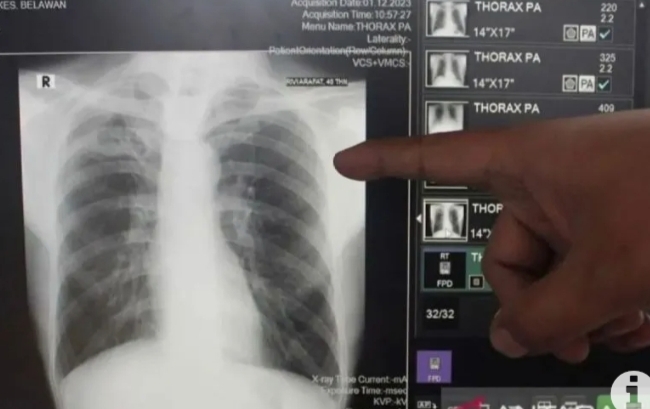

Perwiraone.com Bandar Lampung – Pemerintah Kota Bandarlampung mengatakan kepatuhan penderita terhadap obat yang diberikan oleh fasilitas kesehatan dapat menyembuhkan penyakit tuberkulosis (TBC).Kepatuhan pengobatan TBC dengan empat obat, menjadi kunci dalam penyembuhan penyakit ini,ucap Pelaksana Tugas Kepala Dinas Kesehatan Kota Bandarlampung Desti Mega Putri Rabu 14 mei 2025

Ia menjelaskan, pengobatan TBC dengan empat obat sudah mencukupi. Saat ini, obat anti Tuberkulosis (OAT)/Fixed Drug Combination (FDC), yang merupakan obat kombinasi dosis tetap, di dalam satu tablet berisikan empat obat yaitu Isoniazid, Rifampisin, Pirazinamid dan Ethambutol, bahwa obat tersebut diproduksi menjadi satu tablet, untuk memudahkan penderita meminum obat TBC agar tidak terlalu banyak tablet obat yang diminum,Hal ini menjadi terobosan di pengobatan TBC ucapnya.

“OAT/FDC TBC membantu mengurangi jumlah bakteri Mycobacterium tuberculosis yang menyebabkan penyakit TBC. Obat ini membantu mengatasi gejala TBC, seperti batuk, demam, dan kehilangan berat badan,” kata dia.